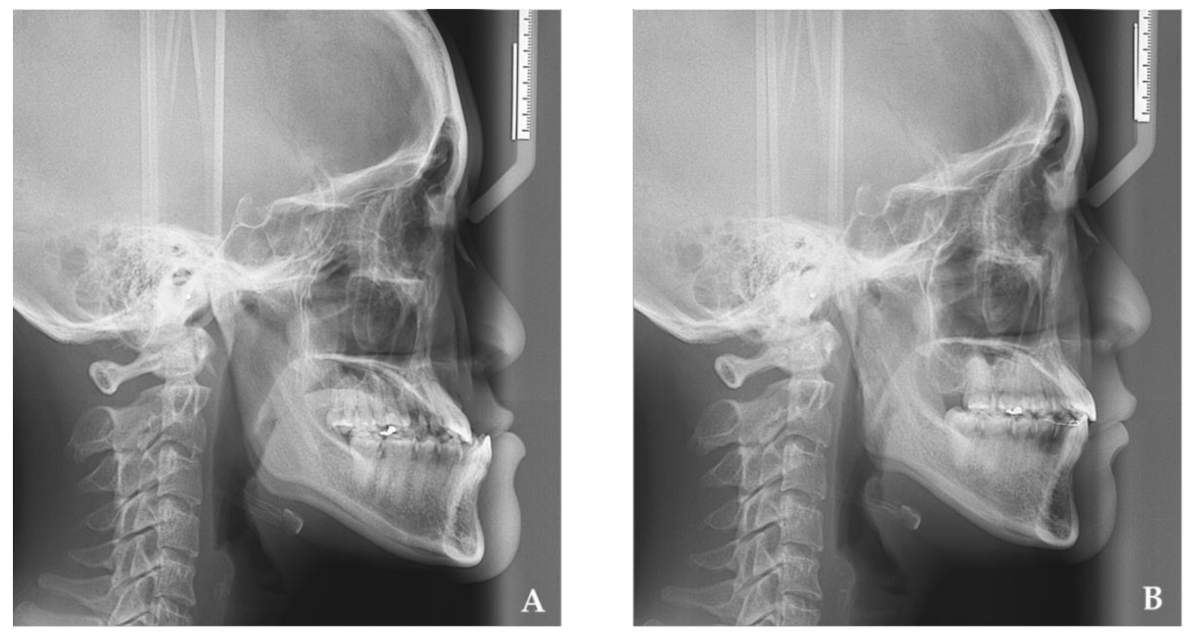

Changes in Tongue Area, Pharyngeal Area, and Pharyngeal Airway Velocity after Correction of Mandibular Prognathism

2. Materials and Methods

3. Results